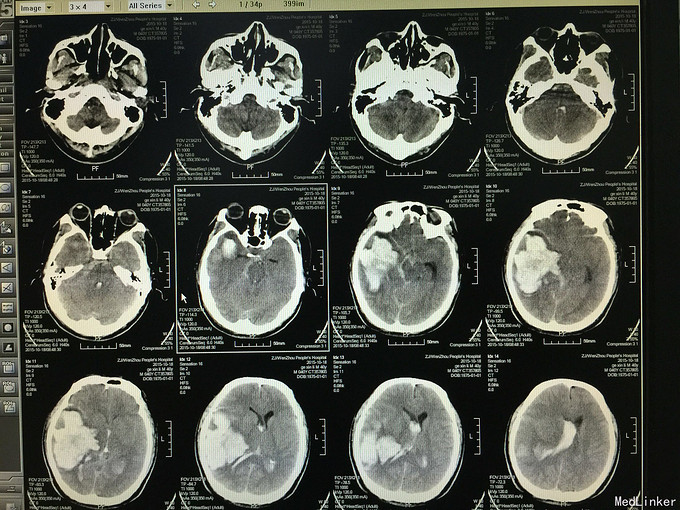

突发意识不清3小时来院,有脑疝前期表现

gcs计5分,双侧瞳孔不对称,左侧偏袒,左侧病理征阳性

行开颅血肿清除加动脉瘤夹闭,图一术中可见动脉变异,依次为后交通动脉、脉络膜前动脉、钩动脉。图二为术后复查cta,提示动脉瘤位于脉络膜前动脉穿脉络裂后的远端。